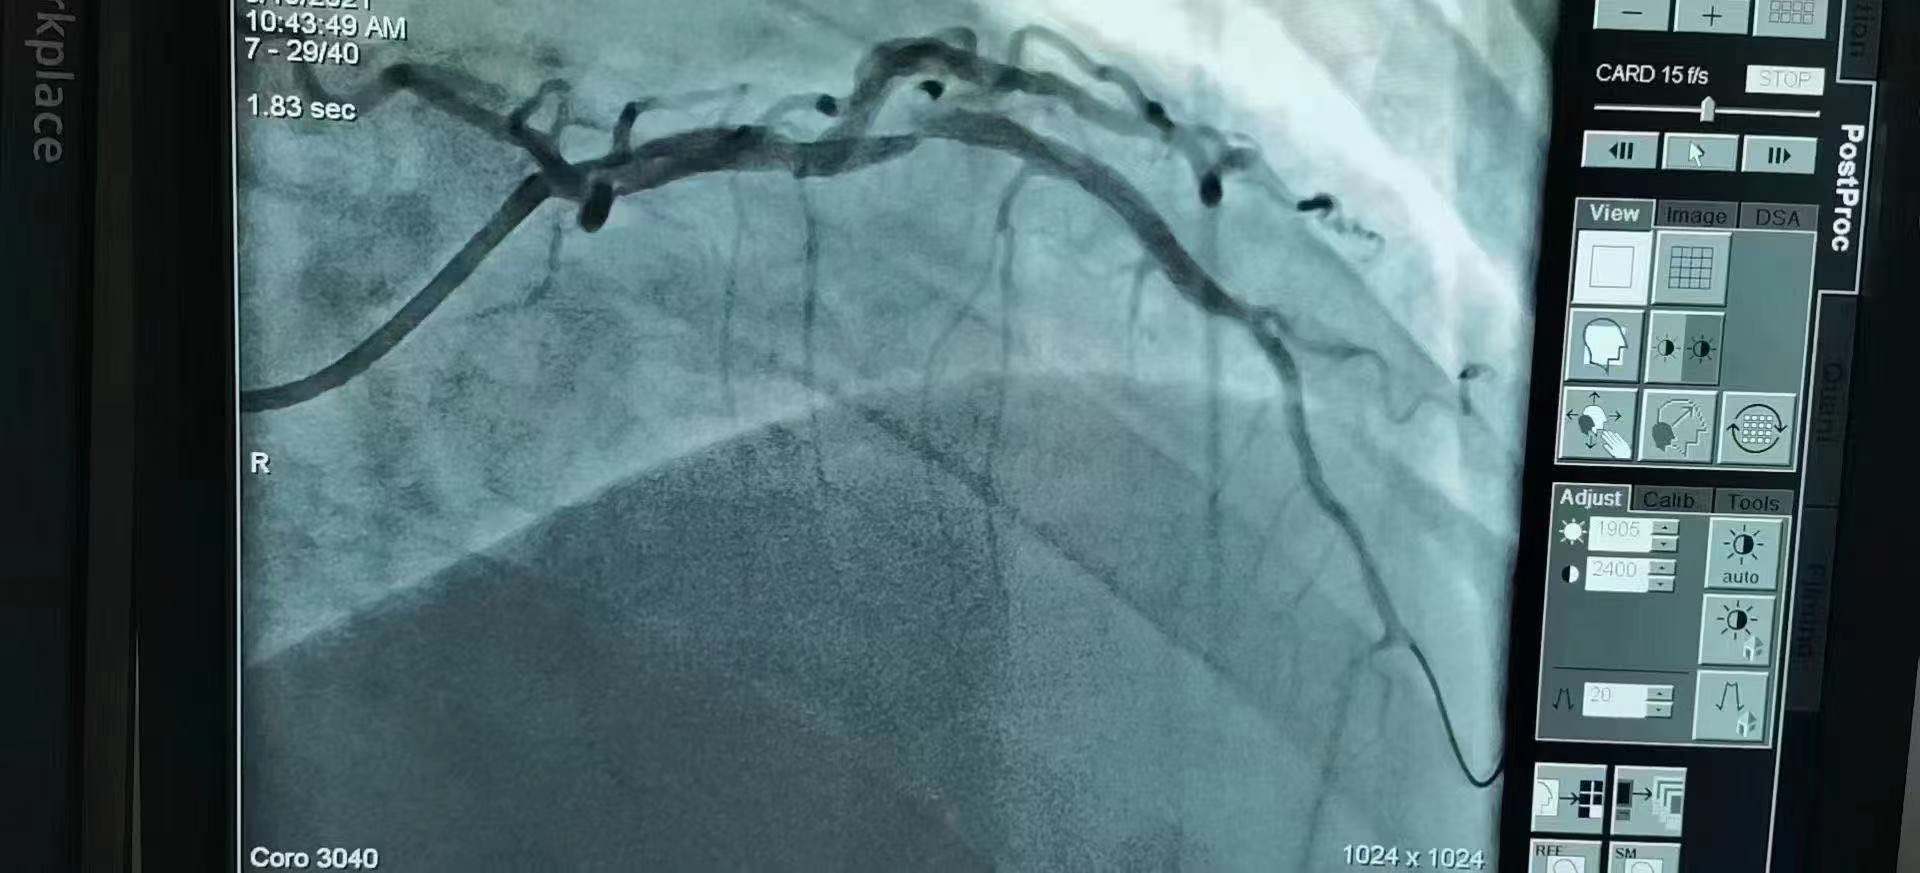

青島市第三人民醫(yī)院 李曉主任團隊成功為患者植入Xinsorb生物可吸收支架!

祝賀 青島市第三人民醫(yī)院  李曉主任團隊成功為患者植入Xinsorb生物可吸收支架!